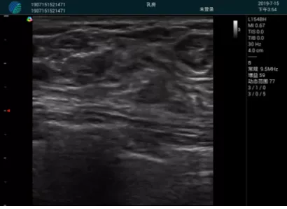

清晰顯示腺體內低回聲快影,邊界清晰,包膜較光滑

確定進針路徑并實時監(jiān)測抽吸針與腫塊位置關系

抽吸針進入腫塊內部進行旋切

抽吸過程中可見腫塊明顯縮小,并根據腫塊位置改變針道位置

抽吸旋切后再進行超聲復查,原腫塊區(qū)域未見殘留組織及出血